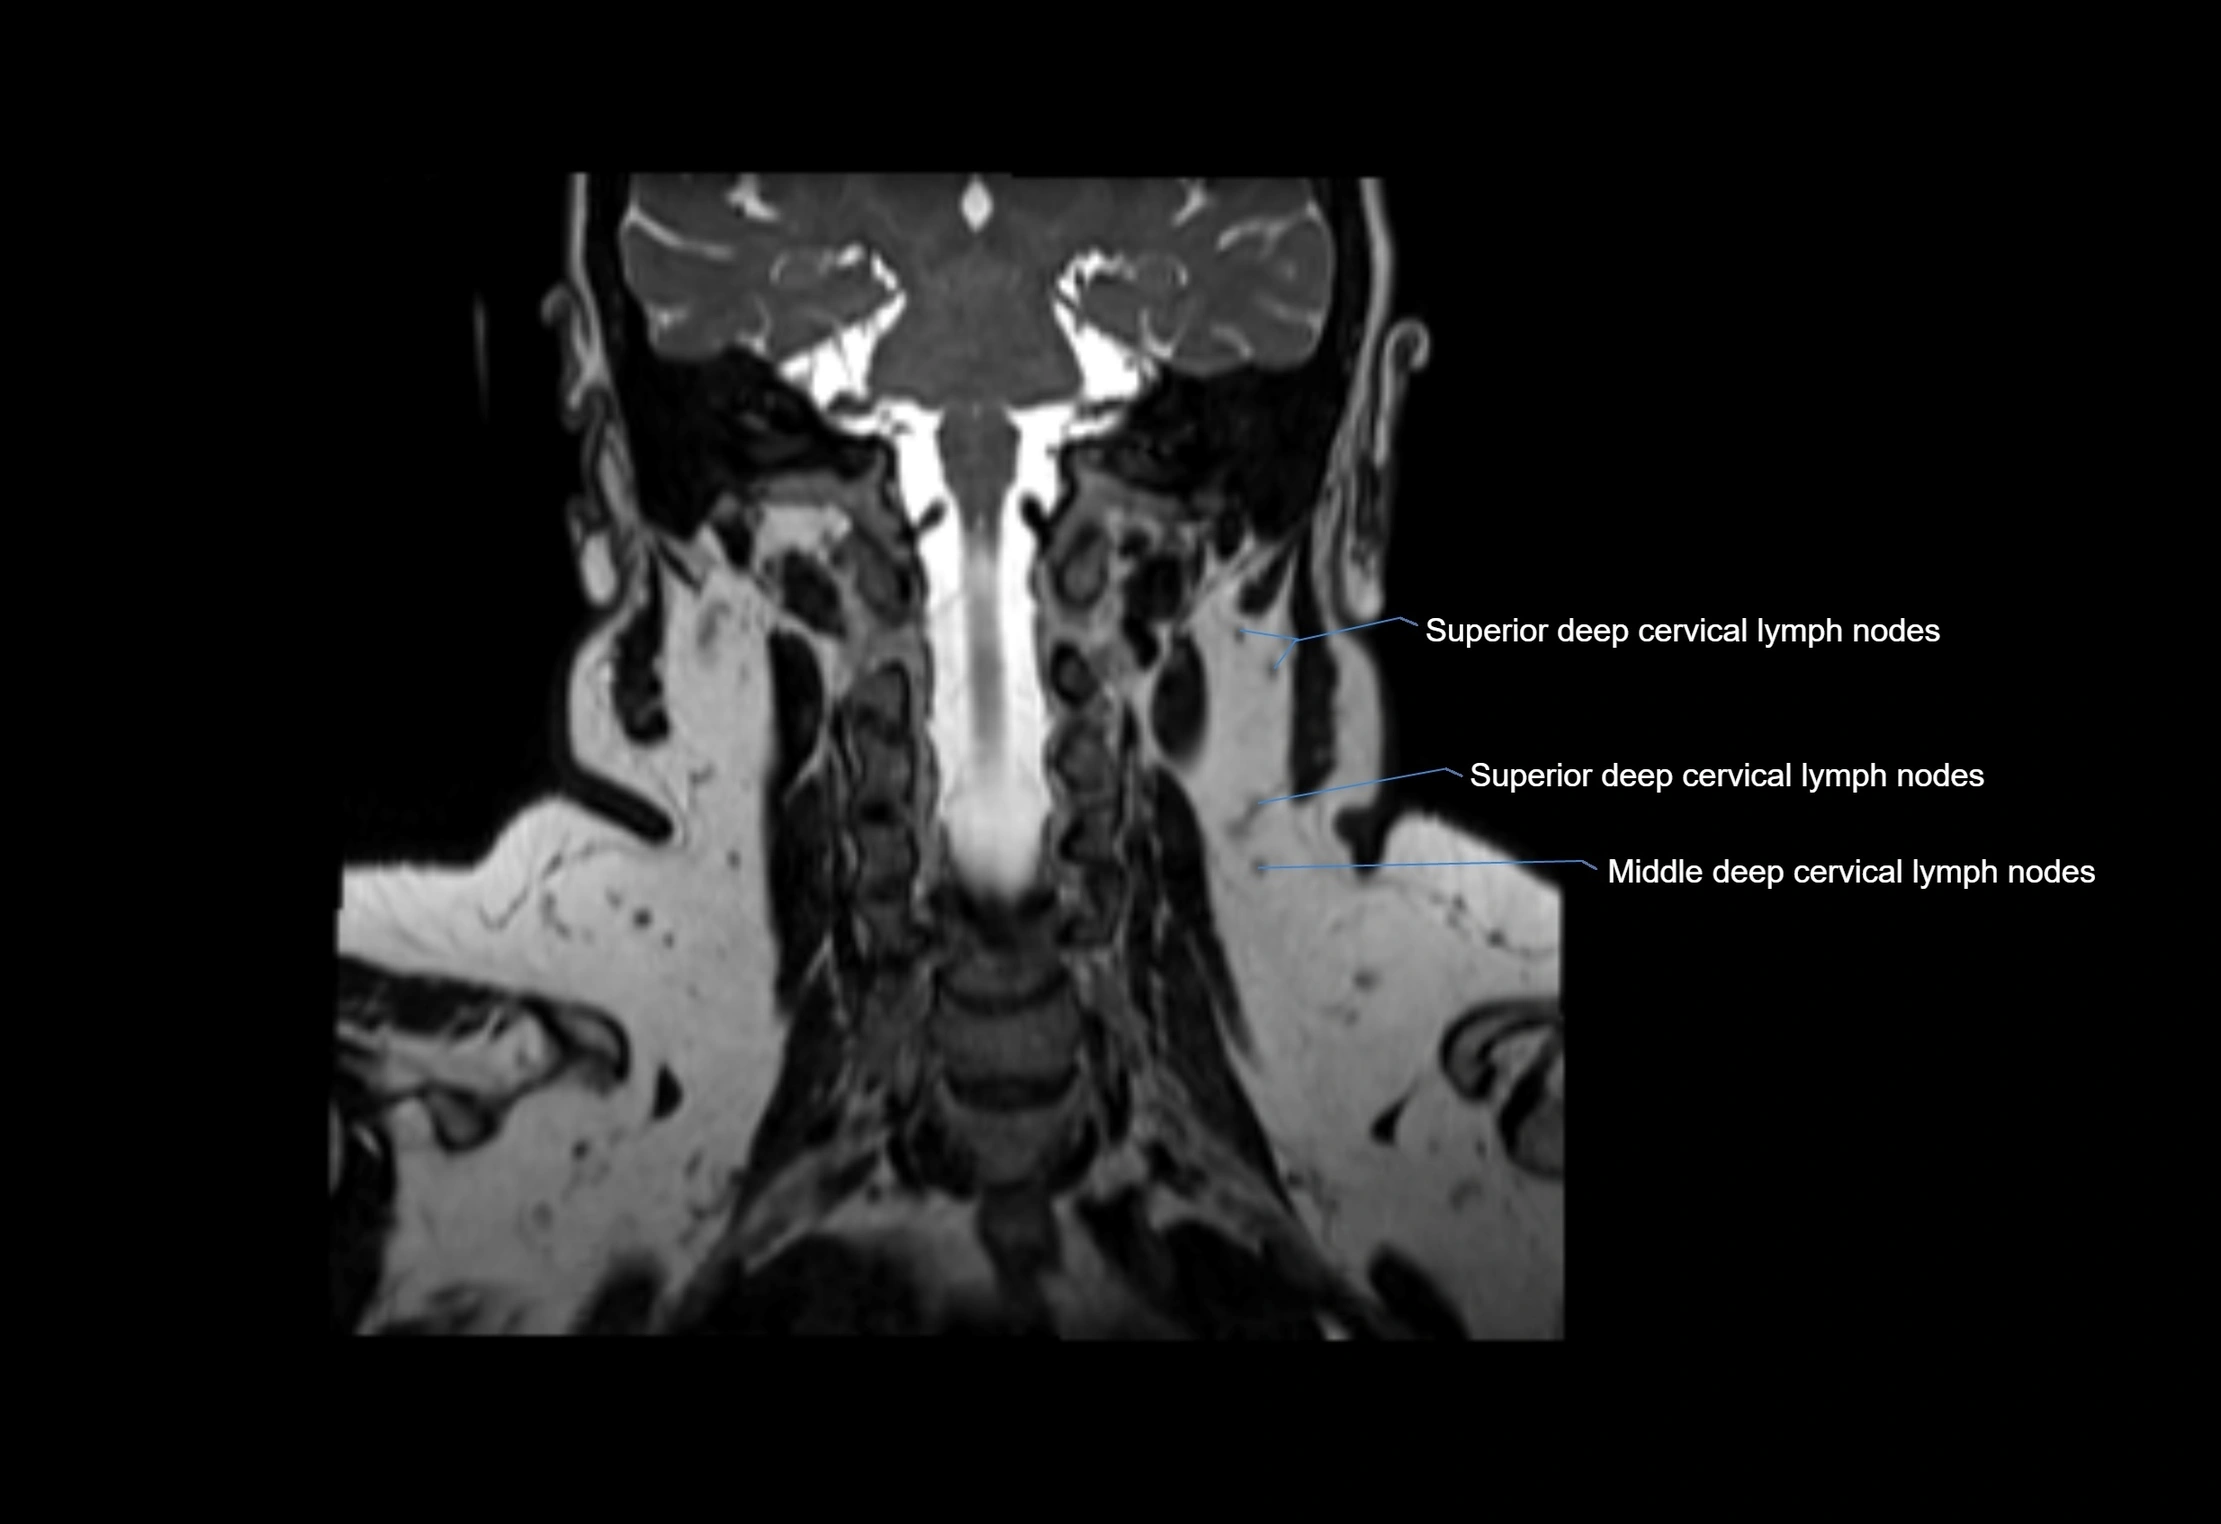

Accessory lymph nodes are small, secondary lymph nodes located along the main facial and cervical lymphatic chains, often adjacent to primary lymph nodes, such as preauricular, submandibular, or occipital nodes. They are typically less than 5 mm in diameter, embedded within subcutaneous fat or connective tissue, and may be variable in number and location. These nodes provide additional filtration and immune surveillance for lymph collected from the face, scalp, and neck regions. Accessory lymph nodes are usually non-palpable in healthy individuals but may enlarge in response to infection, inflammation, or metastasis, making them clinically significant.

• Found along primary lymph node chains, including preauricular, submandibular, parotid, and occipital regions

MRI Appearance

T1-weighted images:

• Normal accessory nodes appear as small, oval hypointense to intermediate signal structures within subcutaneous fat

• Surrounded by hyperintense fat, enhancing contrast for visualization

• Pathological nodes may appear enlarged or rounded, sometimes with cortical thickening

T2-weighted images:

• Nodes show intermediate signal, with surrounding fat bright

• Useful for detecting edema, inflammation, or infiltration

• Fatty hilum may appear slightly hyperintense relative to cortex